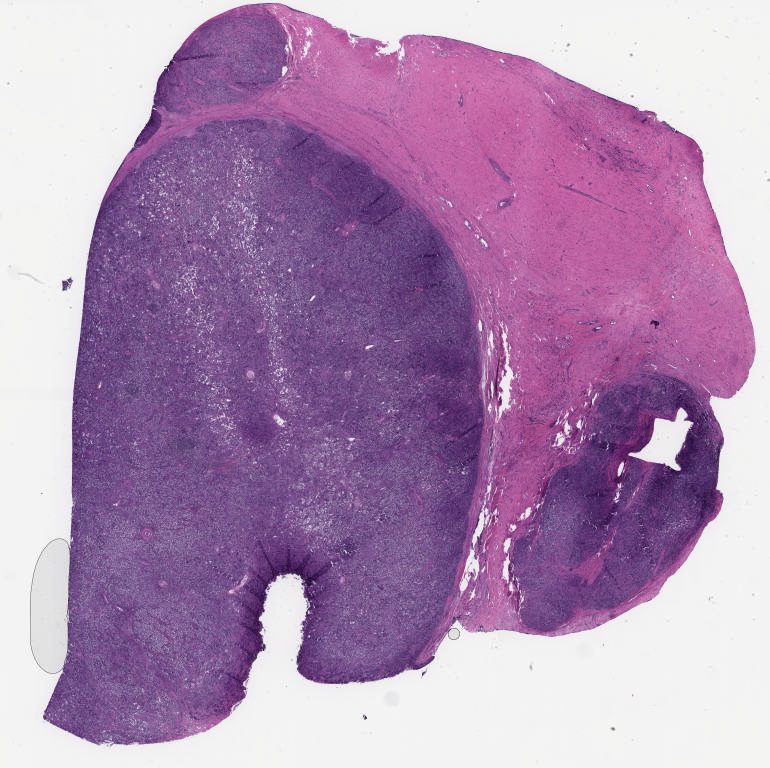

501787.svs

40X